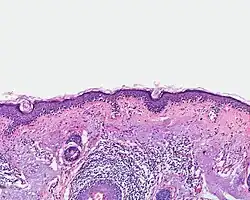

Histologisches Präparat eines malignen Melanoms

Ein Arzt mit entsprechender Erfahrung kann meist durch Sichtung der verdächtigen Hautpartie feststellen, ob es sich um ein malignes Melanom handelt oder nicht. Im Zweifelsfall wird das verdächtige Hautareal im Ganzen (in toto) mit einem entsprechenden Sicherheitsabstand entnommen und unter dem Mikroskop untersucht. Kleinere Gewebeproben sollte man nur entnehmen, wenn eine komplette Exzision nur schwierig möglich ist und man Zweifel an der Benignität hat, da zur feingeweblichen Diagnosestellung bzw. zur Tumordickenbestimmung die gesamte Läsion beurteilt werden sollte. Daneben wird kontrovers diskutiert, ob durch die Entnahme von nur einem kleinen Anteil des Tumors die Gefahr einer Streuung (Metastasierung) über die Blutbahn oder die Lymphe zu groß wäre. Weiteres zu diesem Thema weiter unten.

Die Diagnose des malignen Melanoms erfolgt anhand der histologischen Untersuchung (feingeweblichen Untersuchung unter dem Mikroskop) klinisch auffälliger Pigmentmale und sollte vor dem Hintergrund der klinischen Angaben erfolgen. Neben Patientenalter und klinischem Erscheinungsbild der Läsion sollten dabei auch Entnahmestelle der Gewebeprobe und gegebenenfalls Angaben zur Wachstumsgeschwindigkeit oder einer Farbänderung Berücksichtigung finden.

Um alle zur Einordnung als gut- oder bösartige Läsion erforderlichen Merkmale histologisch beurteilen zu können, sollten Pigmentmale möglichst vollständig entfernt werden. Dabei werden ein Abstand der Läsion zum Schnittrand von zwei Millimetern und die Entfernung bis in die Subkutis (das Unterhautfettgewebe) empfohlen. In Fällen großer oder schwer zugänglicher Läsionen mit starker kosmetischer oder funktioneller Beeinträchtigung durch eine vollständige Entfernung, z. B. akral (an Händen und Füßen) oder im Gesicht, kann zunächst eine Teilentfernung erfolgen. Ergibt die histologische Untersuchung die Diagnose eines malignen Melanoms, ist nötigenfalls durch Nachexzision ein der Tumordicke angemessener Sicherheitsabstand zu schaffen.[32]

Auch anhand vollständig entfernter Läsionen und in Kenntnis aller notwendigen Angaben kann die histologische Unterscheidung maligner Melanome von gutartigen Nävi durch überlappende Merkmale beider Läsionen jedoch erschwert werden. Verschiedene Kriterien sind auszuwerten und führen je nach Konstellation und Ausprägungsgrad der Veränderungen zur abschließenden Einordnung als gut- oder bösartige Läsion.